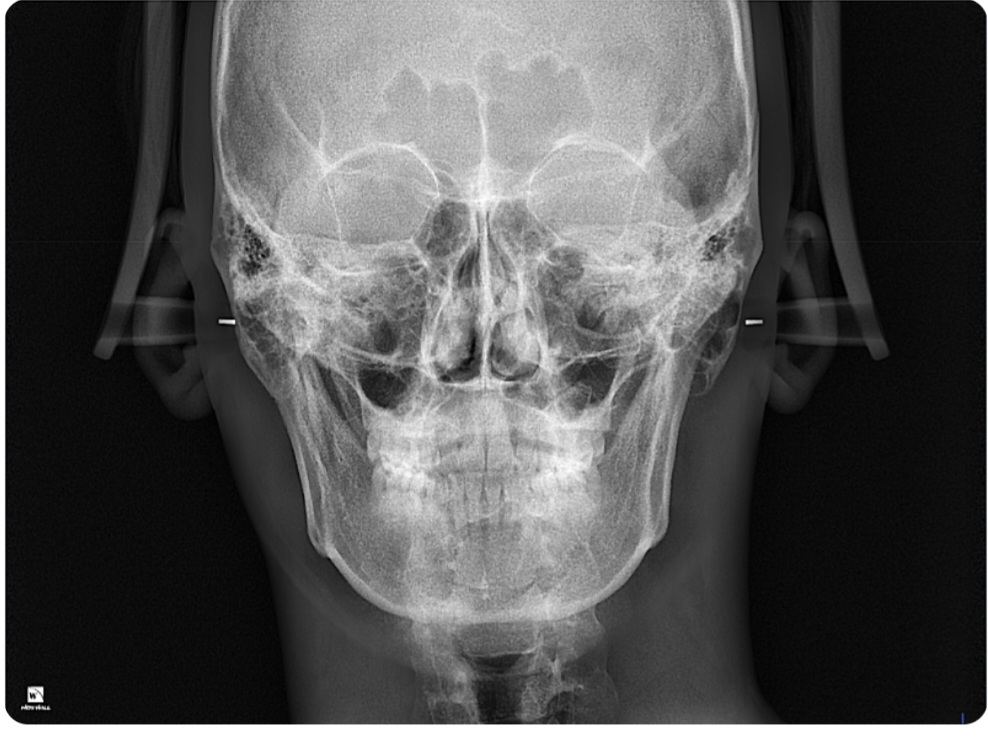

비중격만곡증은 엑스레이로 확인 못하나요?

1.코 비중격만곡증은 엑스레이로 확인못하나요?

2.이비인후과 의사가 코 안쪽을 육안으로 벌려서 확인하면 판단가능한가요?

ct 찍어보면 나오기는 한데 x ray는 연부조직이 잘 보이지 않아서 plain x-ray 하나로 확인하기는 어렵겠습니다.

비내시경으로 들어가도 확인 가능하지만 전체적인 윤곽을 보려면 ct가 낫지 싶습니다.